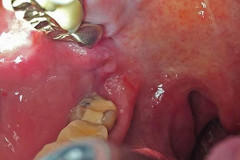

65-ամյա կնոջ լնդի միջից դուրս բերածը շոկի մեջ գցեց բժիշկներին. լուսանկարներ 16+